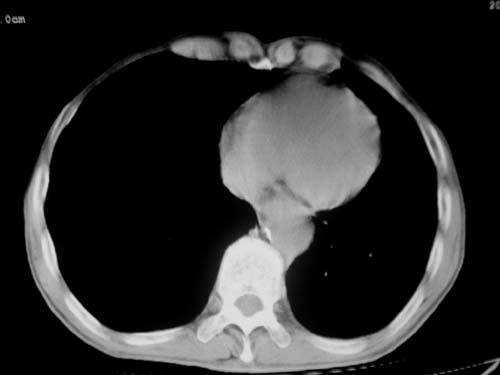

标题: CT19736:男,76岁,咳嗽,胸痛 [打印本页]

标题: CT19736:男,76岁,咳嗽,胸痛

支持左上肺周围型肺癌性并空洞形成伴胸椎转移。

左上沟癌空洞形成并胸椎转移。

考虑癌性空洞并胸椎转移。

空洞内壁有多发结节,支持癌性空洞。

左上肺癌性空洞伴胸椎转移。